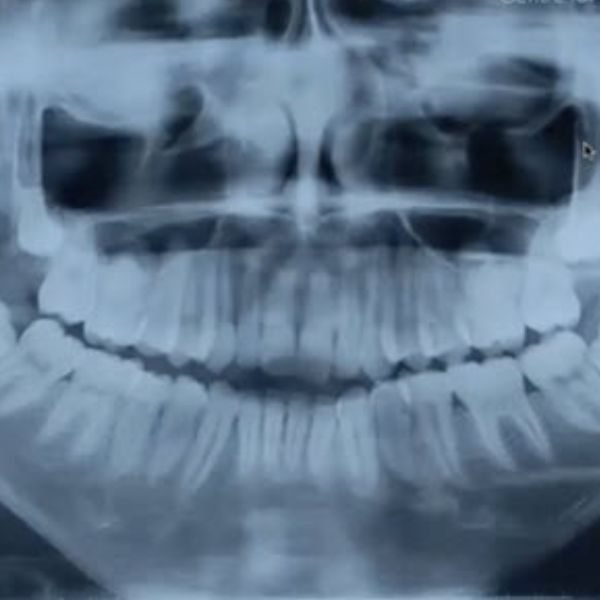

The goals of pediatric Temporomandibular Joint (TMJ) reconstruction are to maintain pain-free mouth opening and prevent re-ankylosis or heterotopic bone formation. We are doing these techniques in small children, but small children will grow. This means adopting a technique that will grow with the children, that would limit asymmetry. There are considerations to differing techniques to TMJ reconstruction in children.

Obviously, children who have undergone TMJ surgery at a very young age will have a small mandible. This decreases the airway space and predisposes these patients to obstructive sleep apnea later on, so we also need to increase the airway space.

This article explores the indications of pediatric TMJ reconstruction using autologous tissues, such as costochondral grafts and transport disc destruction osteogenesis. But what are the strategies to incorporate growth in that, and reduce heterotopic bone at the reconstruction site?

We must also consider TMJ ankylosis, a very challenging area for a TMJ joint reconstruction in children.

Next, let’s consider the classic method of the costochondral graft in TMJ reconstruction. The rationale for this approach is its physiological compatibility to the temporomandibular joint. It maintains ramus height, has growth potential, and acts as an interpositional barrier for the reduction of re-ankylosis and/or heterotopic bone formation.

We have achieved many good results and growth with this method, but a lot of controversies herald the CCG. The growth pattern of the graft is extremely unpredictable, because ankylosis is a common problem.